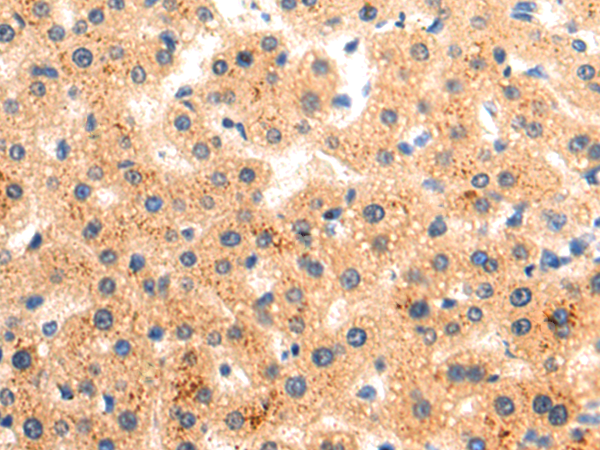

分类: 科研抗体货号: P12753别名: 9-27; CD225; IFI17; LEU13; DSPA2a应用: WB,IHC反应种属: Human, Mouse